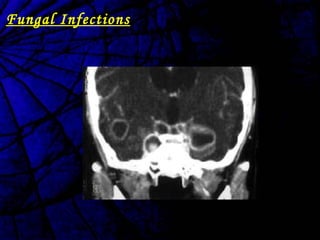

Fungal

Infections

Fungal Infections